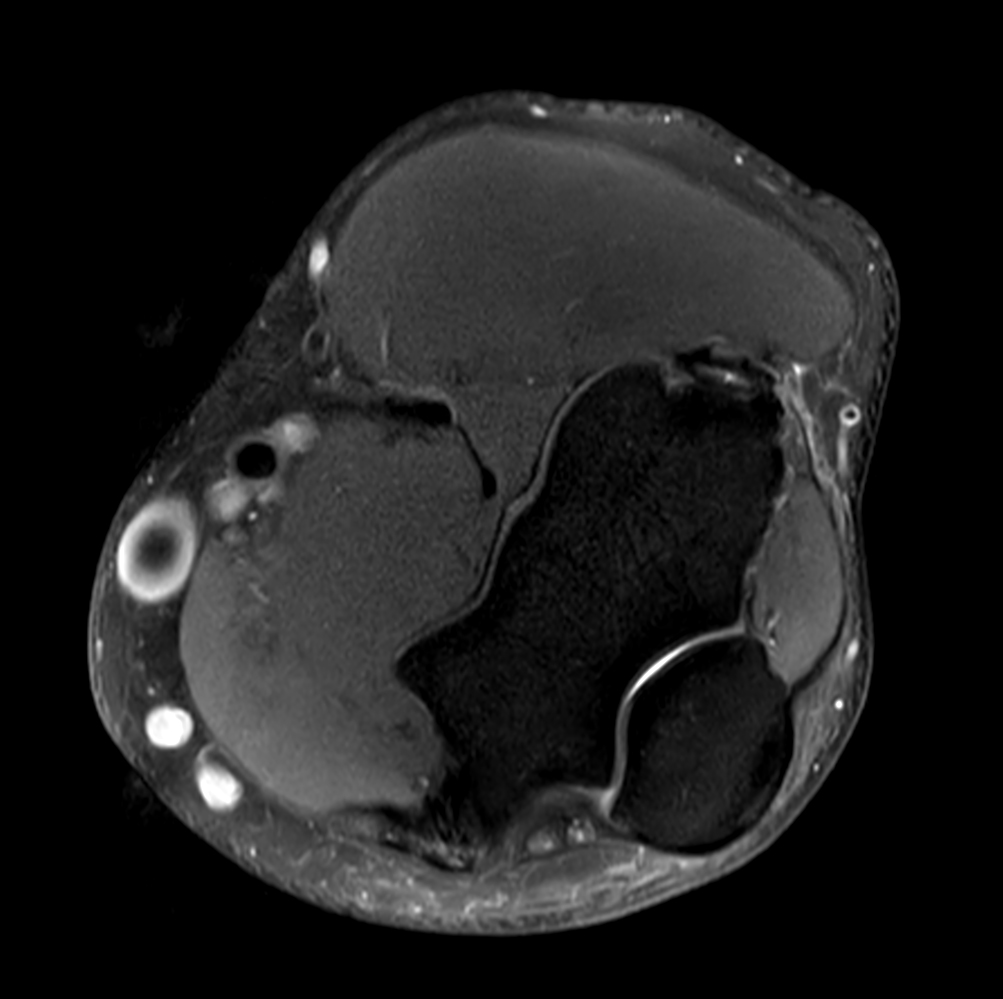

Axial PDw SPAIR